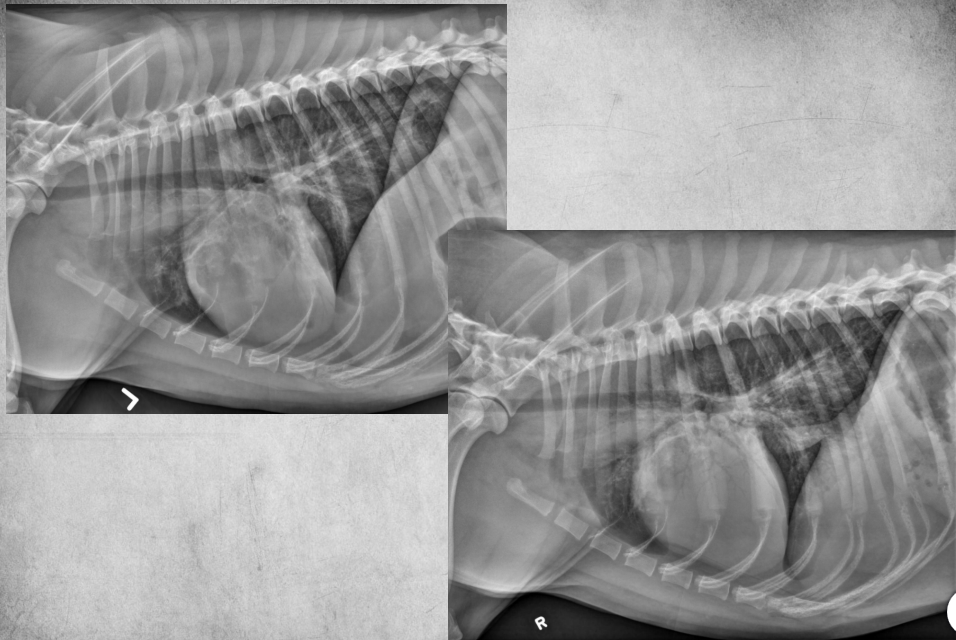

● 7 yo castrated male Golden

Retriever

● Lethargy for last 24h

fat along cranioventral aspect of thorax, maybe fluid too at heart apex.

pericardial effusion: very round heart margin tells you its fluid and not just cardiomegaly.

mild bronchial pattern